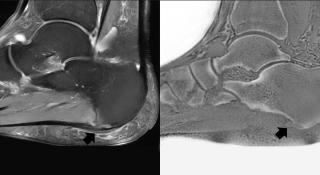

beeld van fasciitis plantaris en hielspoor: links toont de sagittale T2-gewogen opname met vetonderdrukking een verdikte proximale fascia plantaris, een verhoogd T2-signaal met aanliggend wekedelen- en beenmergoedeem

Zie beeld van fasciitis plantaris en hielspoor: links toont de sagittale T2-gewogen opname met vetonderdrukking een verdikte proximale fascia plantaris, een verhoogd T2-signaal met aanliggend wekedelen- en beenmergoedeem. Rechts toont het pseudo-CT-beeld het hielspoor beter.